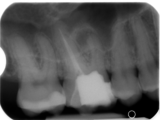

Impressionen zur Offenen Sprechstunde Endodontie (Quelle: Bildarchiv Akademie Karlsruhe)

Zur BildergalerieOffene Sprechstunde Endodontie